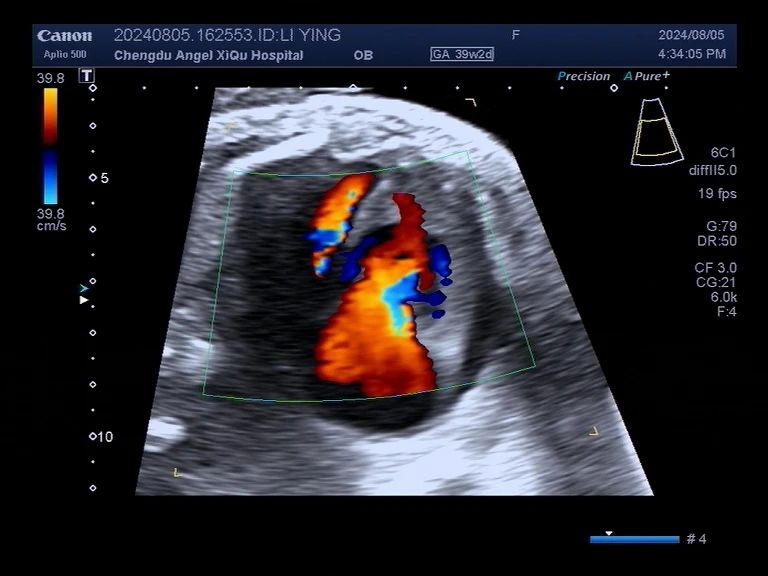

▪l女士胎儿心脏b超

b超提示:胎儿心脏动脉导管提前收缩及早闭伴右心增大、三尖中-重度返流。

经肖兵院长、超声科等多科室联合会诊,考虑胎儿动脉导管提前收缩或早闭,情况很危急,建议立即终止妊娠。这个宝宝的动脉导管接近闭合,这就如同一扇不知道什么时候就会关闭的门,一旦关闭,宫内胎儿的生命就岌岌可危。跟时间赛跑,抢在“关门”前让宝宝安全出生是保证安全的唯一方法。